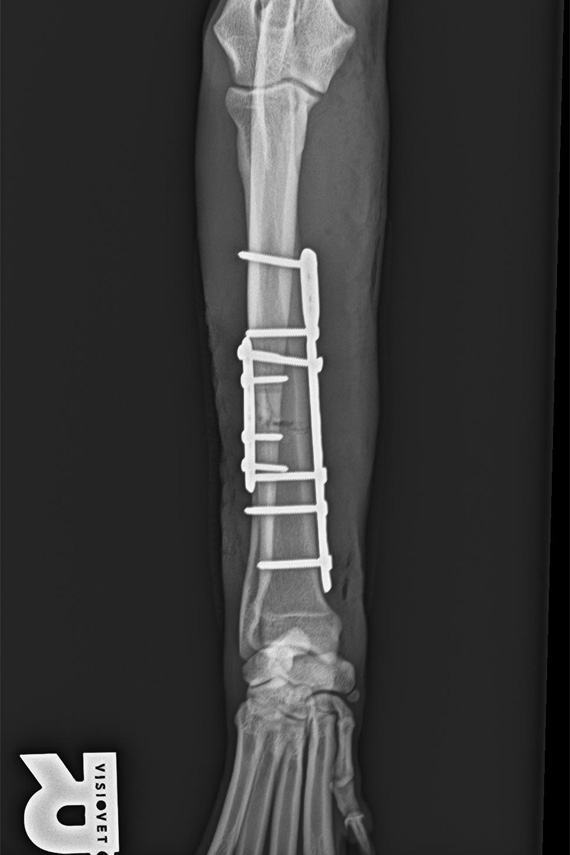

Radius Ulna Querfraktur Hund

Radius Ulna Querfraktur bei einem Hund

Versorgung Radius Ulna Fraktur

Radius und Ulna wurden jeweils mit einer eigenen Platte verplattet.

Ulna Fixateur post-op

Diese Versorgung empfiehlt sich bei größeren und aktiven Hunden.